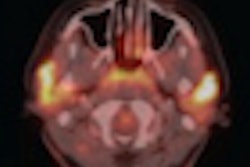

Sites performing SPECT imaging also still must submit technetium-99m (Tc-99m) SPECT phantom images.